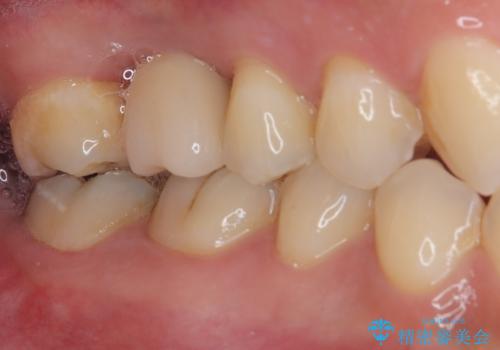

インプラント処置は、抜歯即時埋入を行い、十分な安定性が確認できたため、当日仮歯を装着しました。

インプラントが生着するのを待っている間に反対側の根管治療を行い、左右同時に補綴治療を行いました。

補綴治療後3ヶ月での経過は良好で、引き続き経過観察を行っていきます。